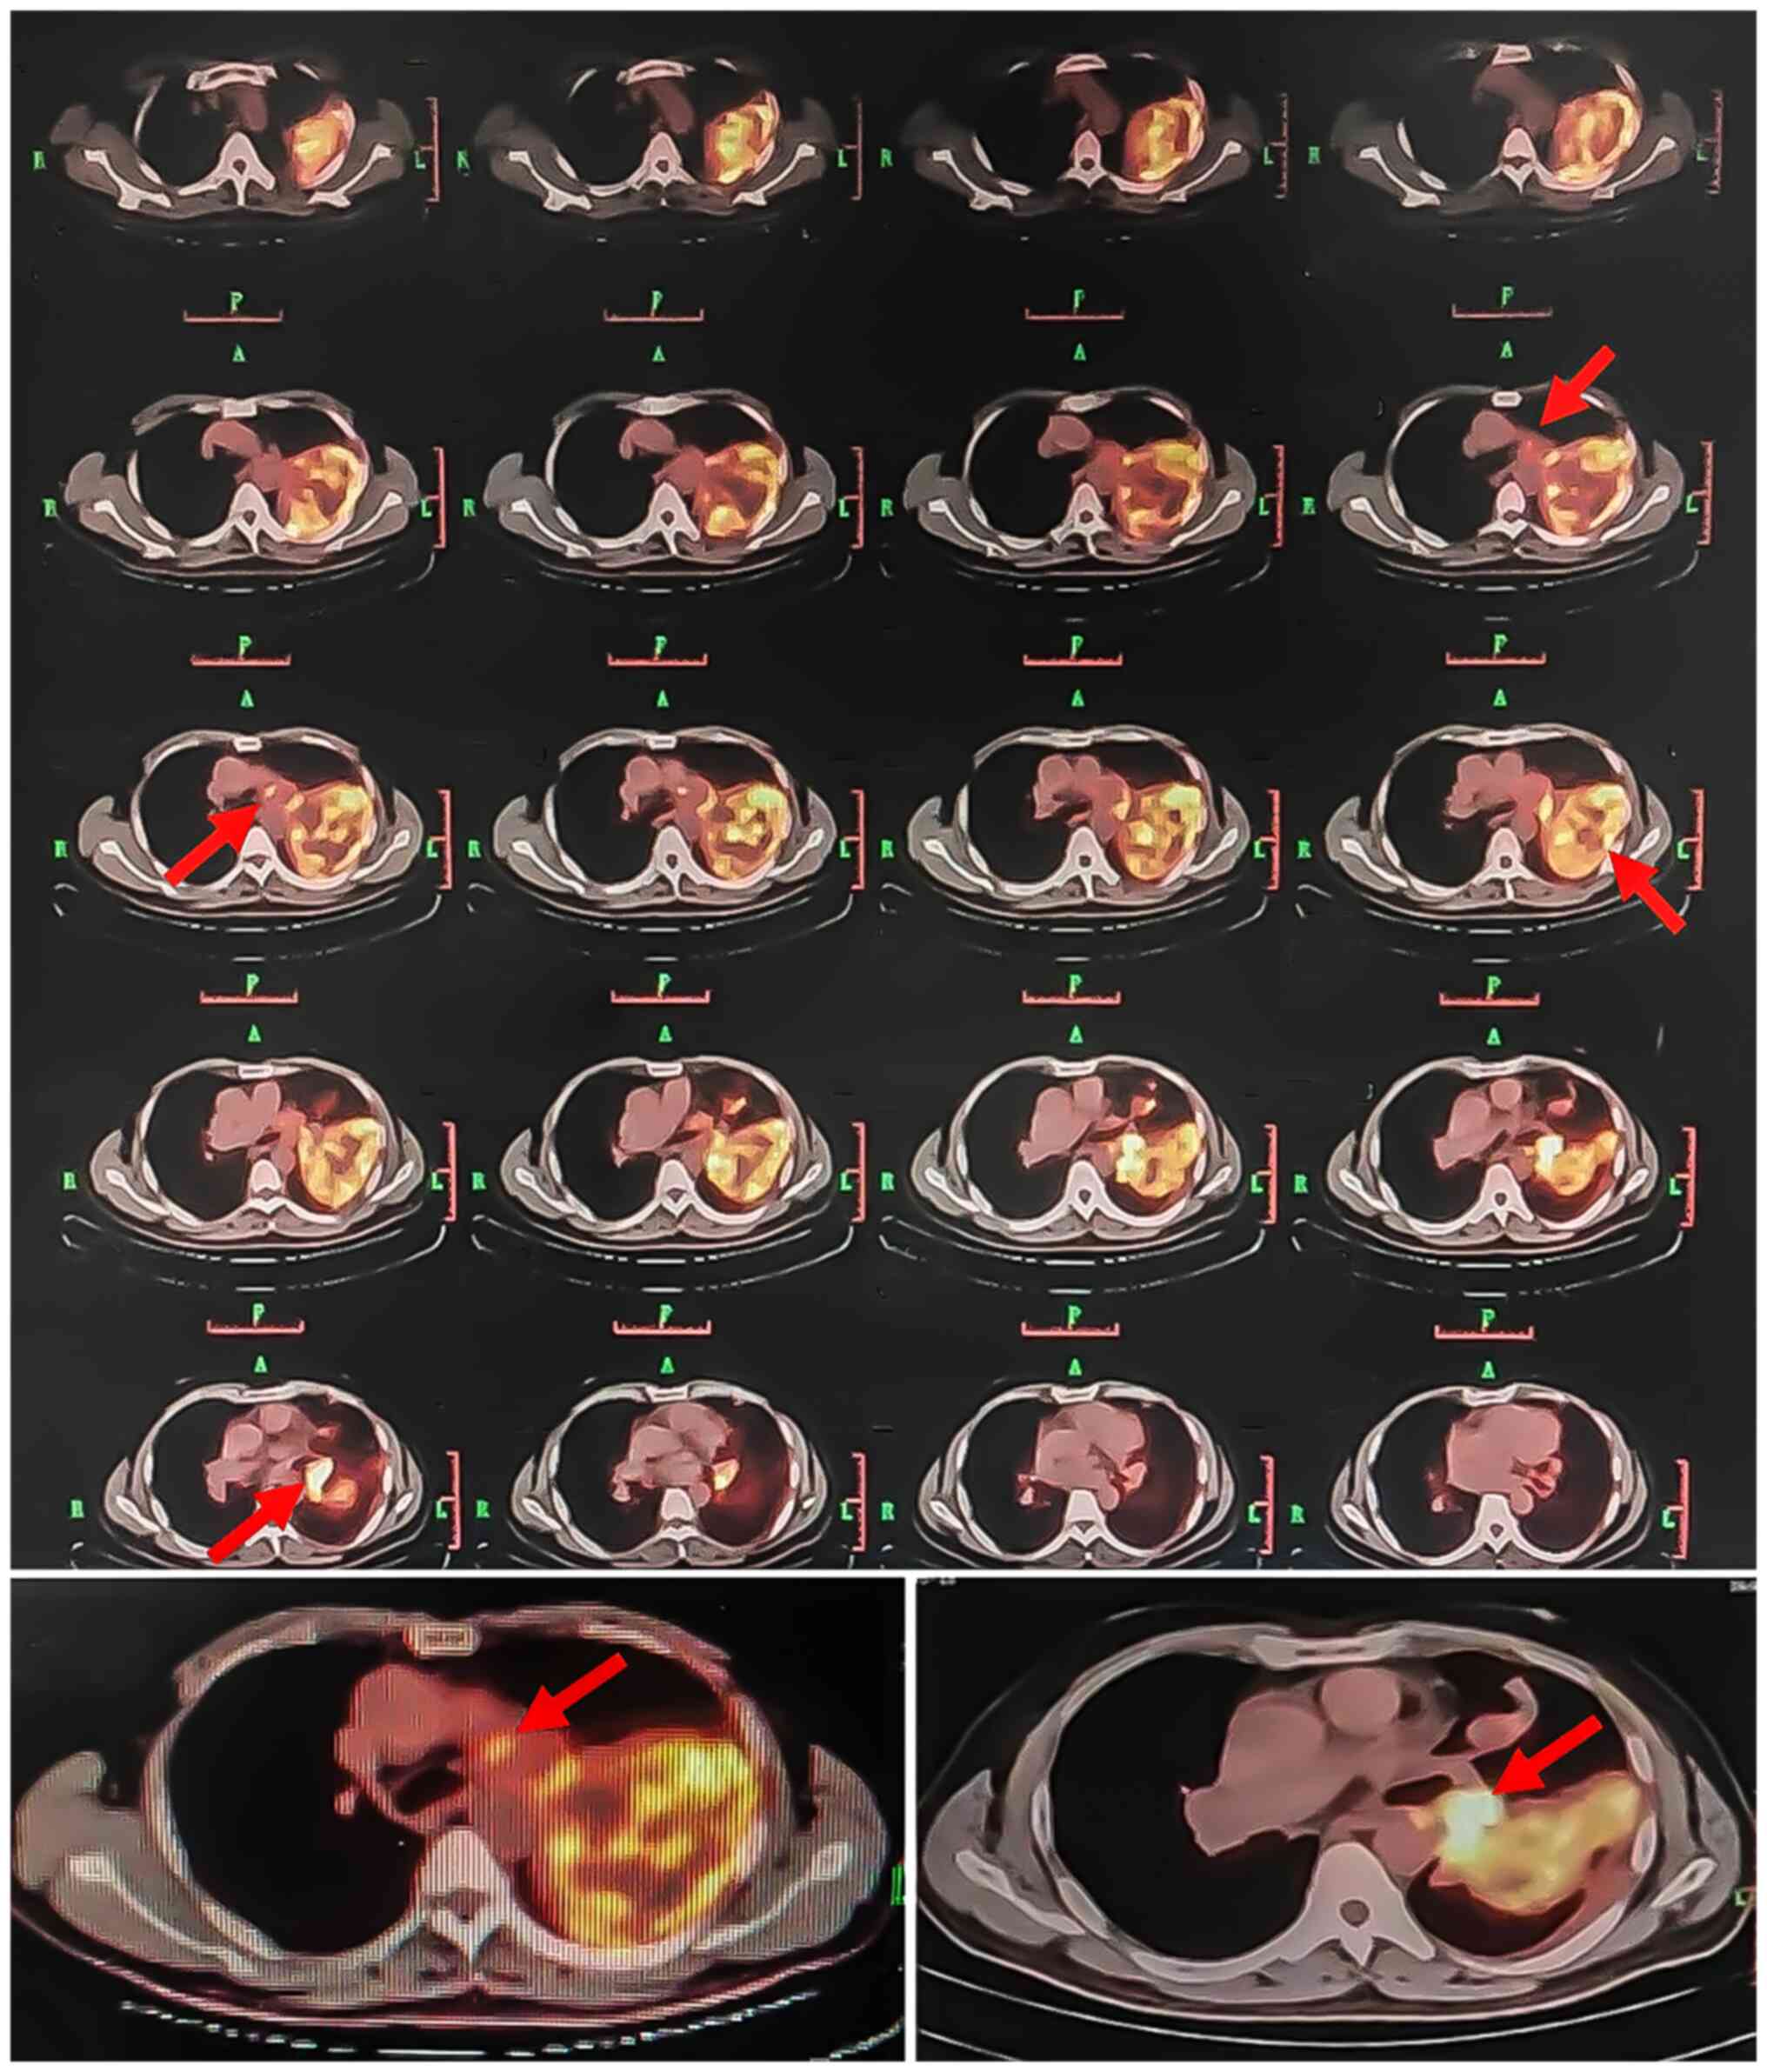

During the hospitalization period, right heart catheterization, which is a possibly helpful test for cases with similar presentation, e.g. to rule out the possibility of chronic thromboembolic pulmonary hypertension, was planned. However, the patient did not consent to undergo this examination. Re-examination of the pulmonary artery CTA (Fig. 3) revealed that the left pulmonary artery was completely embolized, whereas the right main and middle pulmonary arteries were partially embolized. Lung perfusion imaging (Fig. 4) indicated that blood perfusion was reduced in the majority of the left lung and in the anterior segment of the right upper lobe, which was consistent with pulmonary embolism. The patient underwent CT-guided percutaneous puncture biopsy and positron emission tomography (PET)/CT (Fig. 5), which revealed the following: Soft tissue mass in the area of the left pulmonary artery and slightly increased metabolism; space-occupying upper lobe of the left lung, slightly increased metabolism; nodules in both lungs; left hilum lymph nodes, increased metabolism; thickened left pleura with a small amount of effusion in the left pleural cavity.

Figure 5.

PET-CT examination after 6 months of anticoagulation. Thickening of the soft tissue in the left pulmonary artery and formation of a mass with mild FDG uptake (the maximum cross-sectional area is ~4.7×3.9 cm); a soft-tissue mass was noted in the upper lobe of the left lung (size, ~11.7×8.6×9.6 cm), with a slightly higher FDG uptake. The lesion was involved the left hilum inwardly and the costal pleura in an outward direction; the upper lobe of the left lung nodule was noted in the tongue (~2.1 cm in diameter) and FDG uptake was mild. The left hilar demonstrated multiple lymph nodes (the larger diameter is ~2.5 cm) and FDG uptake was increased (red arrow). FDG, 18F-fluorodeoxyglucose.

According to previous studies, 18F-fluorodeoxyglucose (FDG) PET/CT may help distinguish PAIS from CPTE based on the maximum standardized uptake value (SUVmax). The SUVmax of PAIS is significantly higher than that of CPTE. When the cutoff value was 3.3, the reported sensitivity, specificity and accuracy were 98.4, 96.8 and 97.8%, respectively (16). However, certain false-negative cases have also been reported. In the reports of Suto et al (17) and Takauchi et al (18), the uptake of FDG in PET/CT used for the diagnosis of patients with PAIS was poor. The histopathology of these cases indicated highly malignant cells with low cellularity and a significant type of interstitial myxoid tissue. In the current case report, the left pulmonary artery exhibited mild FDG uptake (SUVmax 4.2) and increased FDG uptake of the left hilar multiple lymph node (SUVmax 8.1), which supported the diagnosis of PAIS.